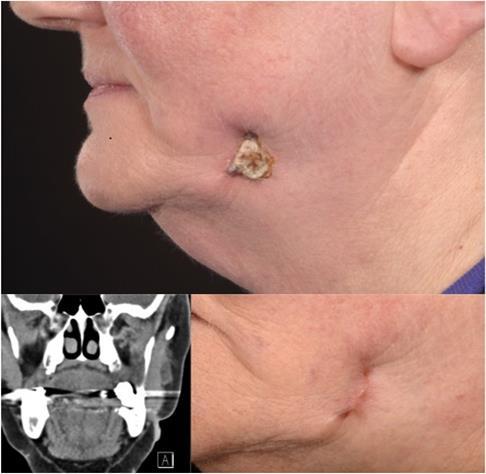

A 70-year old patient was referred to the Dermatology department by her general practitioner (GP) because of a non-healing lesion on her left cheek. She reported that the skin problem originally started in November 2012 when she developed pain and erythema in her left cheek and neck almost overnight. Originally, her symptoms were diagnosed as cellulitis and responded to a course of oral Flucloxacillin. The lesion then subsequently flared up and a biopsy was taken by the GP due to concern it might be a squamous cell carcinoma. The patient had a further two courses of oral Flucloxacillin followed by topical Fucidin cream (Fusidic acid) and Rozex cream (Metronidazol), which both minimally reduced the size of the lesion. On examination, she had an indurated, tethered lesion on the left lower cheek measuring 2cm x 1cm (Figure 1a). This lesion was surrounded by firm tissue, with a red- brown discolouration and there was no evidence of lymphadenopathy. As the patient demonstrated carious teeth, she was referred to the Craniofacial Department for further management. An OPG and CT scan were ordered for further imaging which demonstrated an intact cortex of the mandibular ramus. However, it was noted that superior to the skin lesion, there was a smooth defect in the superficial cortex of the bone around the tip of the root of the last standing molar (Figure 1b). We performed a surgical removal of her lower left last standing molar, debridement of the intraoral infection and associated cutaneous sinus. One week postoperatively, on review, the area has settled considerably. Intraoral, the mucosa has healed well with no evidence of discharge or tenderness on palpation and the cutaneous surface had re-epithelialised.

Figure 1(a-c).Skin lesion pre-operatively, Computed Tomography scan pre-operatively and scar post-operatively

11 months post operatively, the patient’s lesion had fully healed and she was very pleased with the aesthetic result. (Figure 1c).